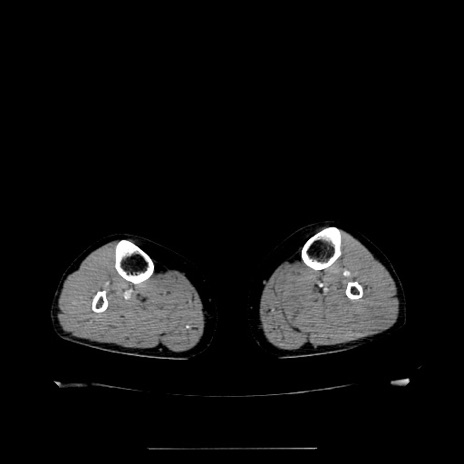

症例5(横断像)

【症例】70歳代女性

【主訴】お腹が張る

【現病歴】1週間くらい前から腹部膨満の自覚あり。昨日夜から増悪したため、本日救急外来受診。

【身体所見】意識清明、BT 36.5℃、BP 165/106mmHg、HR 80bpm、SpO2 98%、腹部:膨満、軟、自発痛・圧痛なし、触診にて不快感あり、腸蠕動音:減弱

【データ】WBC 12600、CRP 1.04